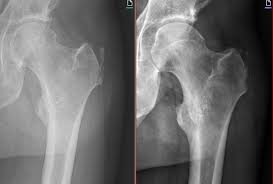

- X-Rays: X-rays can help rule out other causes of hip pain, such as fractures or arthritis.

- MRI (Magnetic Resonance Imaging): An MRI provides detailed images of the soft tissues, tendons, and bursae. It can reveal inflammation, tendon tears, or degeneration.

- Ultrasound: An ultrasound scan can be used to detect bursitis or damage to the gluteal tendons.